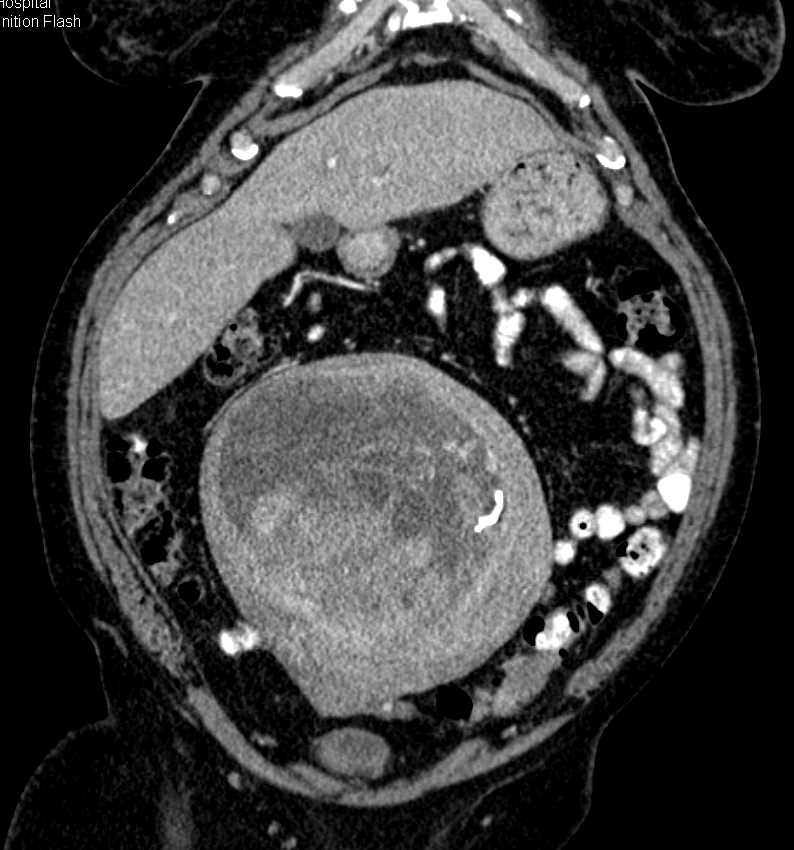

Red degeneration of uterine fibroids in pregnancy Radiology Case

Red degeneration of uterine fibroids in pregnancy Radiology Case from radiopaedia.org

You may experience it as a sharp pain in the abdomen accompanied by. At the lower segment of the uterus, a round heterogeneous structure measuring 11 x 11 x 9 cm with central anechoic material located to the right of the cervix is pushing the cervix. To determine pregnancy outcomes in those previously treated for uterine fibroids, including with uterine artery embolisation and ulipristal acetate. Pain is one of the most reported symptoms of fibroids during the latter part of pregnancy: Pain of carneous degeneration of a uterine. Although red degeneration of a uterine myoma during pregnancy is. Apr 25, 2016 · submucosal fibroids, on the other. Seeing red degeneration in uterine fibroids in pregnancy: Difficulty with bowel movements, or other bowel symptoms.

Those women who are familiar with the symptoms of fibroids will find the symptoms from degeneration are even worse. Before pregnancy degenerating fibroid discharge. At the lower segment of the uterus, a round heterogeneous structure measuring 11 x 11 x 9 cm with central anechoic material located to the right of the cervix is pushing the cervix. Two began to degenerate while i was pregnant last year. Throughout pregnancy, pain is the most common issue caused by fibroids, and may occur in the pelvis, abdomen, lower back, hip, or down the leg. To discuss the mode of delivery in women with a previous myomectomy. Severe cramps, similar to menstrual cramps. For most women studied, fibroids stayed the same size after the second trimester or even shrunk during the third trimester. As the pregnancy progresses, large.